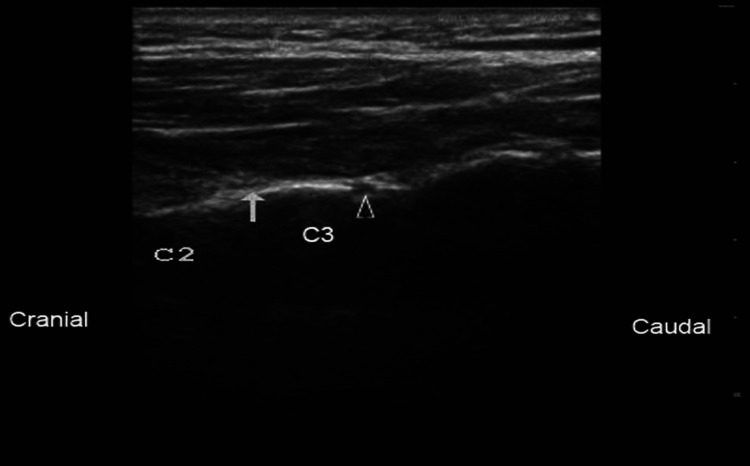

Ultrasound is readily available and inexpensive and can be readily deployed to help guide many interventional procedures. Figure 1 and Figure 2 are among the many examples of how advanced imaging has made greater and more precise interventions possible.

Ultrasound has become an increasingly important tool in pain medicine in recent years. Traditionally, fluoroscopy has been the gold standard for guiding interventional pain procedures, but it has limitations, such as only visualizing bony structures. Conversely, ultrasound provides real-time, high-resolution images of soft tissues, allowing for more precise needle placement and reduced procedural complications. By combining ultrasound with fluoroscopy, clinicians can obtain a more complete picture of the patient’s anatomy and perform more accurate procedures.

In the 1970s, nerve stimulators were introduced as a more accurate method for nerve blocks. These devices use electricity to stimulate nerves so the practitioner can identify the needle’s correct location. However, ultrasound started to be used in regional anesthesia after the 1990s. The adoption of ultrasound in pain medicine required time for ultrasound technology to become more sophisticated and user-friendly.

As ultrasound technology advances, we can expect to see even more improvements in its use in pain medicine. New technologies, such as fusion imaging and artificial intelligence, are being developed to make ultrasound more accurate and effective. As these technologies mature, ultrasound will likely take its rightful place in pain medicine.